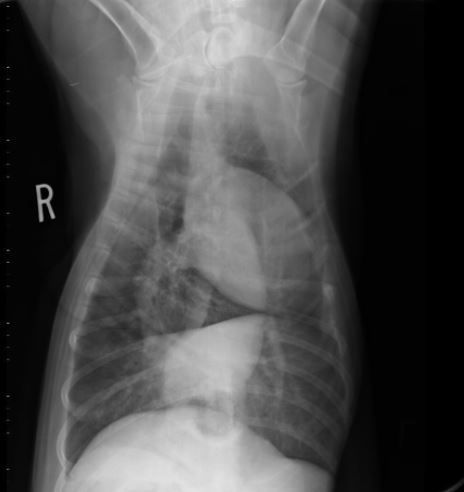

Artifact? Fix?

There are two rads in that image… one with the glove is the artifact and the one without it is normal.

Density threshold - metal object change the gray-scale to exclude your wanted anatomy .

Remove metal object